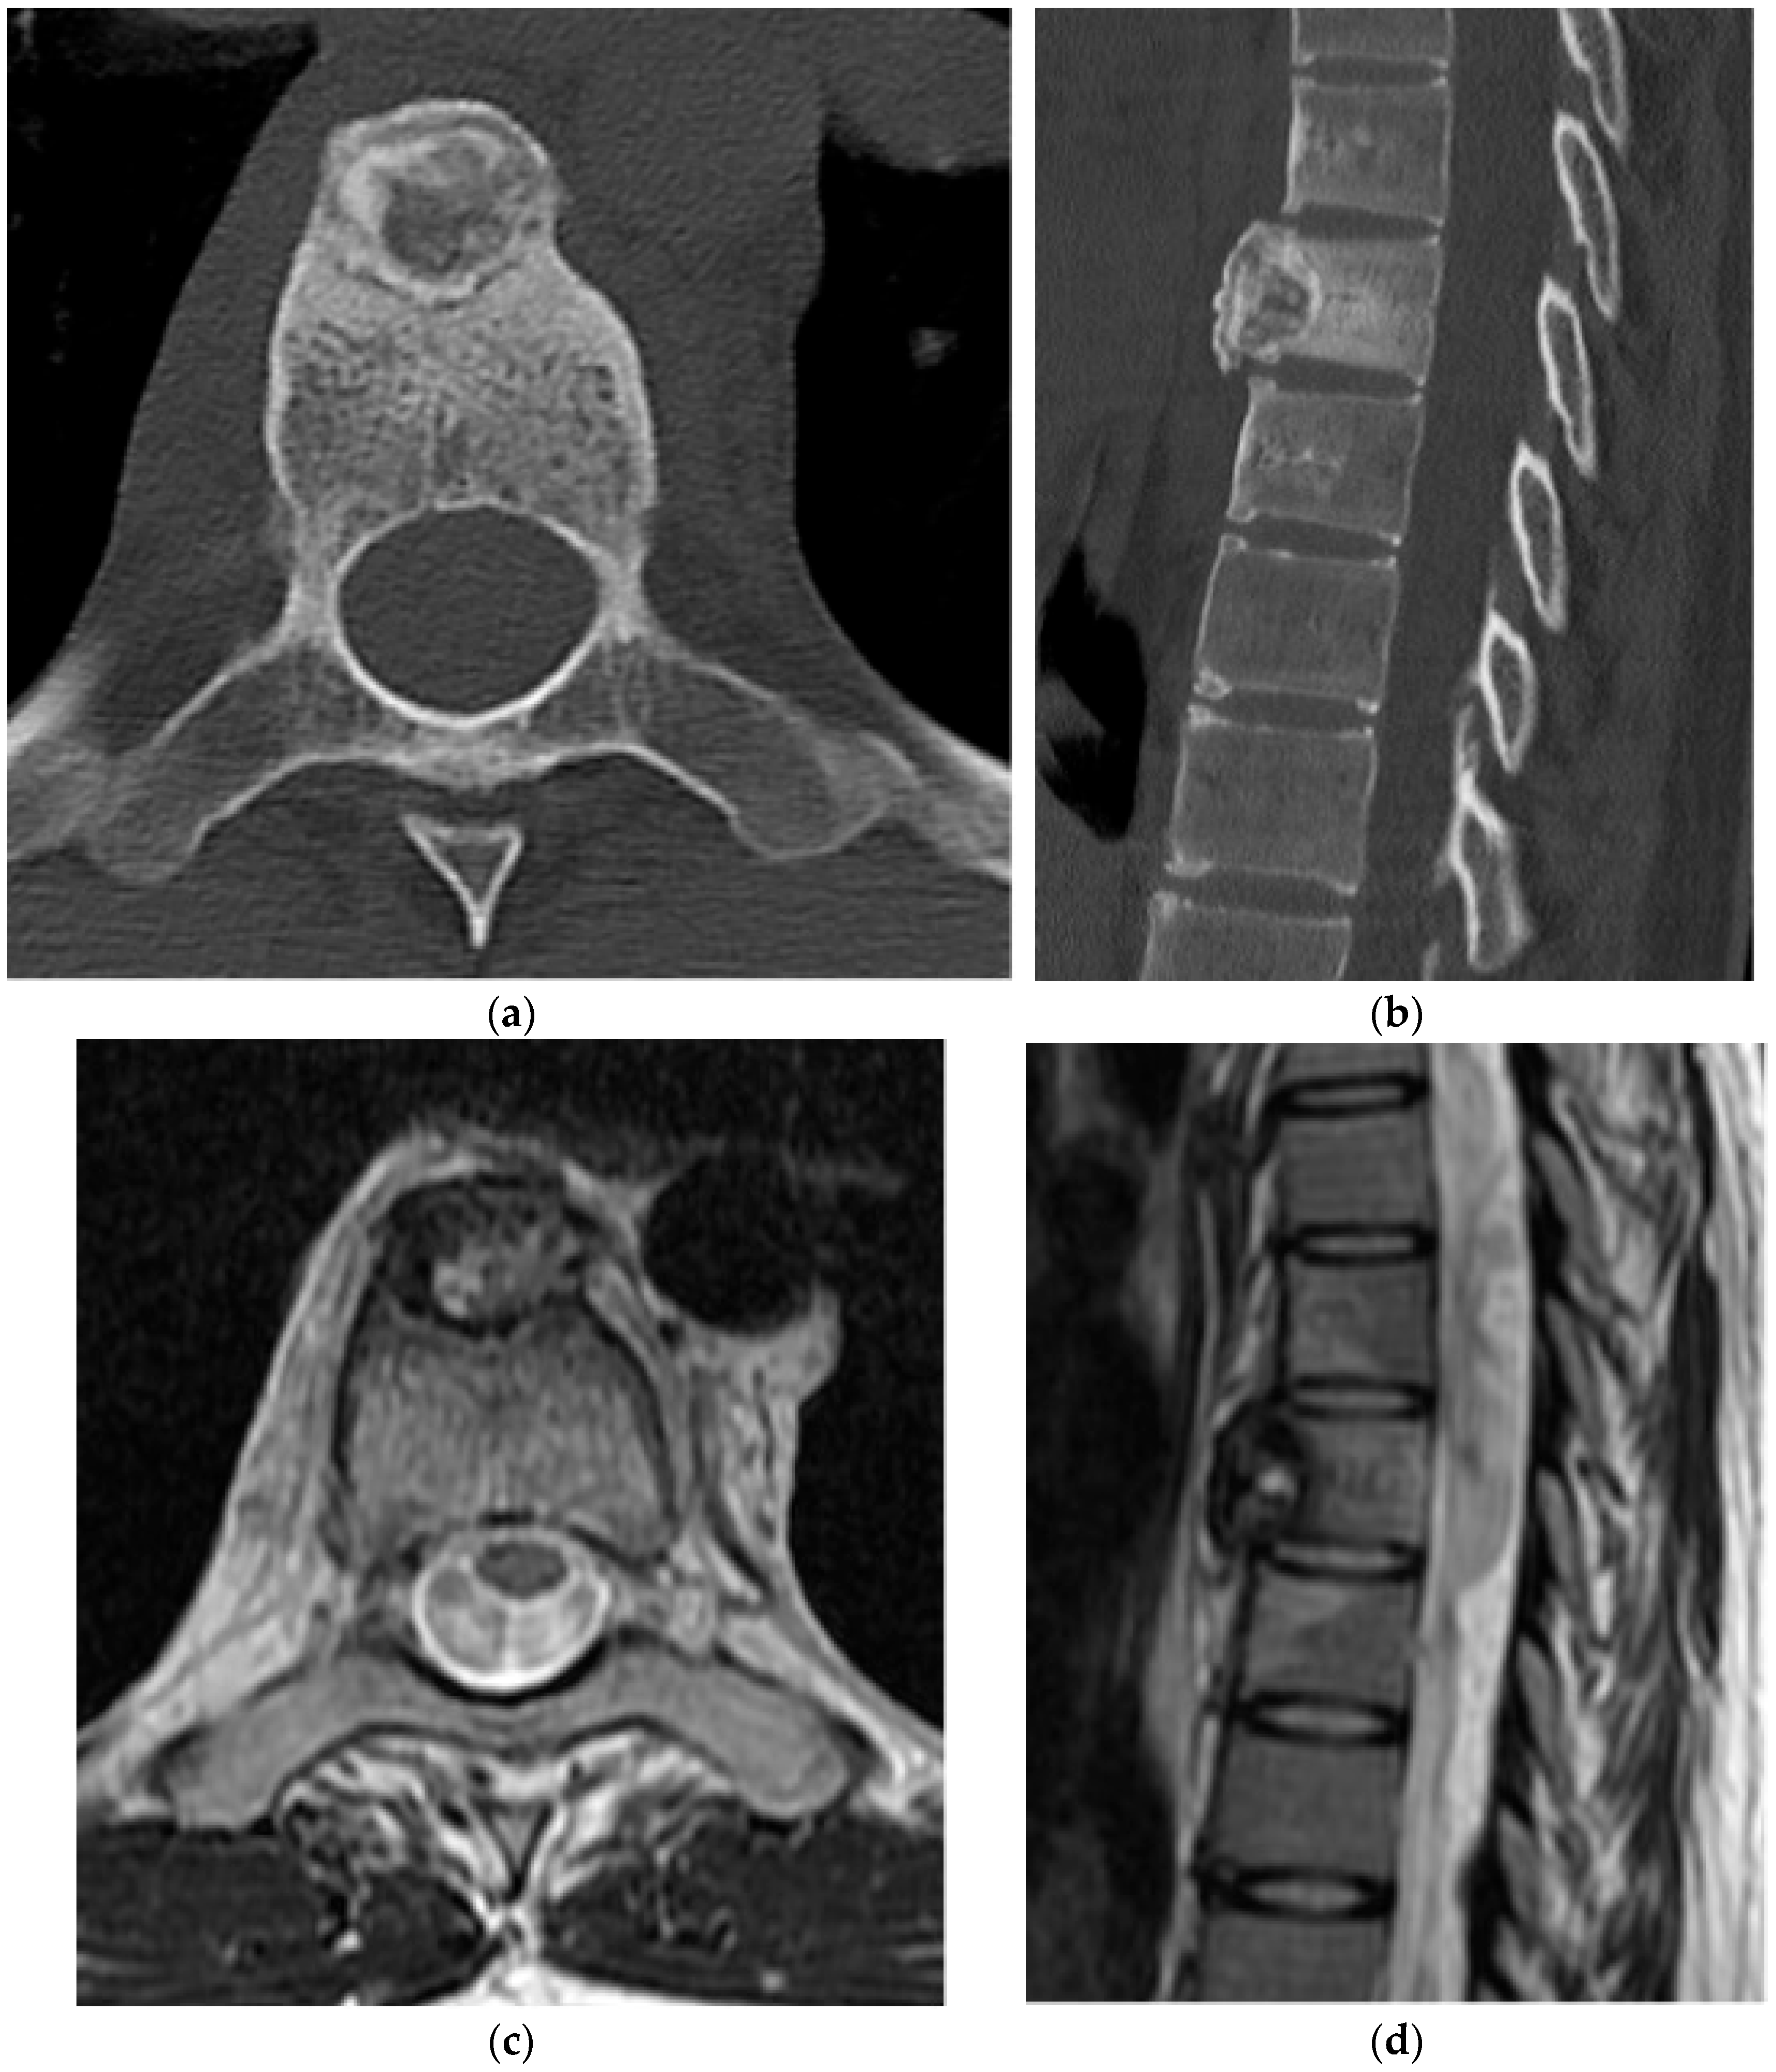

2.2.3. Chondrosarcoma

2.3. Notochordal